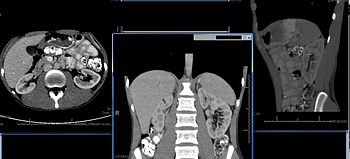

Imaging Studies

Imaging studies are important in the evaluation of structural renal disease caused by urinary tract obstruction, renal stones, renal cyst, mass lesions, renal vascular disease, and vesicoureteral reflux.

Imaging techniques used most frequently include renal ultrasound and helical CT scan. Patients with suspected vsicoureteral reflux may undergo voiding cystourethrogram (VCUG).